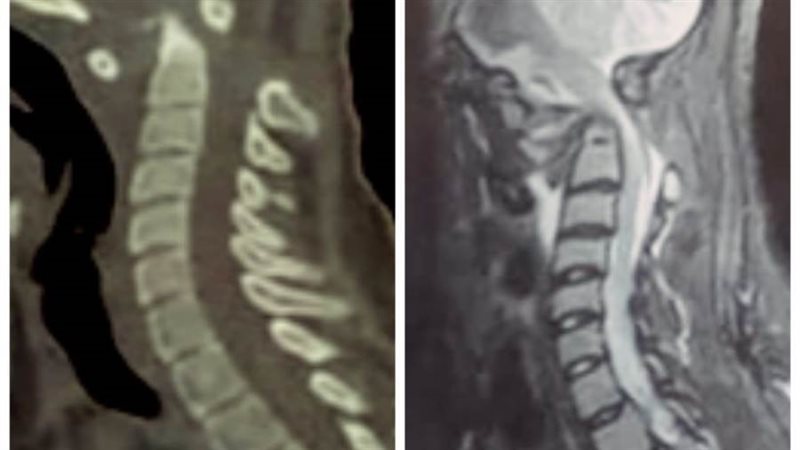

صرح رئيس جامعة سوهاج بأن قسم جراحة المخ والأعصاب بالمستشفى الجامعي نجح في إجراء تدخل جراحي نادراً ويعد الأول من نوعه فى صعيد مصر، لفتاة تبلغ من العمر ١٨ عاماً، وتعانى من مرض خلقي الانغماس القاعدي مع عدم ثبات قاع الجمجمة في الاتصال بالفقرات العنقية، وهي من الحالات النادرة الحدوث، حيث أدى هذا المرض إلى إصابة الفتاة بشلل رباعي حاد نتيجة الضغط على الحبل الشوكي وجذع المخ بقاع الجمجمة.

وقال الدكتور مجدي أمين القاضي عميد كلية الطب البشري ورئيس مجلس إدارة المستشفيات الجامعية إنه تم على الفور حجز المريضة بالقسم والتجهيز للتدخل الجراحى لتوسيع قاع الجمجمة مع استعدال الاعوجاج الفقرات العنقية وإعادتها الى الوضع التشريحي الطبيعي وتثبيتها بقاع الجمجمة.